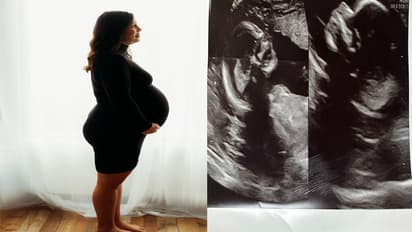

हेल्थ डेस्क. अमेरिका में रहने वाली 32 साल की केल्सी हैचर (Kelsey Hatcher) के पास दो यूट्रस है। हैरानी की बात यह है कि उनके दोनों यूट्रस में बच्चे पल रहे हैं। दो यूट्रस होने की स्थिति को डिडेल्फ़िस कहा जाता है जो अपने आप में दुर्लभ है। उसपर से इस तरह की स्थिति "लाखों में से एक" होती है। खुद हैचर और उनके पति कालेब भी इसे लेकर शॉक्ड है कि ऐसा कैसे हो सकता है।

हैचर और उनके पति कालेब बताते हैं कि जब वो आठ हफ्ते की अल्ट्रासाउंड कराने गए तो उन्हें पता चला कि वह दो बच्चों की उम्मीद कर रही थी। उनकी मानें तो हैचर जन्म से ही गर्भाशय डिडेल्फ़िस या डबल गर्भाशय के साथ पैदा हुईं। जिसका अर्थ है कि वह दो गर्भाशय और दो गर्भाशय ग्रीवा उनके अंदर है। 3 बच्चों की मां ने "गुड मॉर्निंग अमेरिका" को बताया,'जब मुझे पहली बार पता चला, तो मैंने सोचा कि क्या मैं ऐसे किसी इंसान से संपर्क कर सकती हूं जो इस स्थिति से गुजरा हो। ये जानने के लिए कि उसका अनुभव क्या थे। लेकिन मुझे लगता है कि मैंने सिर्फ दो ही ऐसे मामले पढ़े हैं जिसमें पूरी तरह अलग गर्भाशय यानी यूट्रस में गर्भधारण हुआ था। ऐसा कोई मामला नहीं था जिससे मैं संपर्क कर सकती थी।

हैचर ने कहा कि उसे 17 साल की उम्र में पता चला कि उसके पास एक डबल यूट्रस है। तीन बार वो प्रेग्नेंट हो चुकी है, लेकिन एक ही यूट्रस में बच्चा था। तीनों बच्चे नॉर्मल तरीक से हुए। वो बताती है कि जब इस बार वो प्रेग्नेंट हुई तो आठ सप्ताह के अल्ट्रासाउंड कराने गई। वहां जब पहली बार अल्ट्रासाउंड हुआ तो नर्स से पूछा एक ही है ना। उसने कहा कि हां जिसे सुनकर मैं राहत की सांस ली। तभी नर्स ने कहा कि एक और यूट्रस है और उसमें भी बच्चा है। पहले तो मैं हैरान हुई और हंसती रही कि ये मजाक है। लेकिन बाद में बताया कि ये सच है। वहीं हैचर के पति ने बताया कि जब हैचर ने फोन करके बताया कि वो दो बच्चों की उम्मीद कर रही तो मेरी पहली प्रतिक्रिया थी कि मुझे नहीं पता कि इस बार क्या अलग हुआ, लेकिन यह अजीब है।

हैचर की देखभाल करने वाले गायनो डेविस और डॉ. श्वेता पटेल ने कहा कि दोनों शिशुओं को भाई-बहन माना जाता है। उन्होंने बताया कि संभवतः ऐसा हुआ कि उसने अलग-अलग ओव्यूलेशन किया और प्रत्येक फैलोपियन ट्यूब में एक एग आया, जिसका अर्थ है कि प्रत्येक फैलोपियन ट्यूब के नीचे आ रहा है। इस दौरान स्पर्म दोनों एग को निषेचित किया और वो अपने अपने यूट्रस में चले गए।हैचर वर्तमान में लगभग 34 सप्ताह की गर्भवती है और उसकी 25 दिसंबर को उनकी डिलिवरी डेट है।